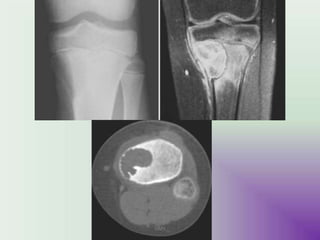

IMAGING

UMY

• MRI

• Ideal for the evaluation of transphyseal or

transcortical extension.

• Demonstrating associated surrounding bone

marrow oedema.

•These lesions have signal typical of cartilage: T1

- lesion itself is of low to intermediate signal T2

/ STIR - lesion is of intermediate to high signal

• Fluid-fluid levels may occasionally be seen .

image

• T1 T2 STIR